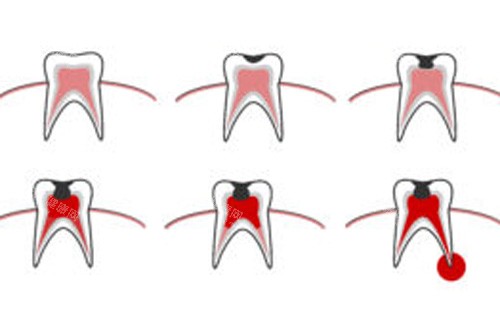

对于日常口腔保健和小问题处理,致美口腔提供了多种基础治疗服务。更基础的补牙项目,使用普通树脂材料的费用从178元到480元不等,具体价格取决于牙齿损坏程度和所需补牙面积大小。如果是后牙的较大面积缺损,可能需要选择更高强度的补牙材料,价格会相应有所上调。

针对牙齿大面积缺损但牙根尚存的情况,医院提供桩核冠修复服务。金属桩核加全瓷冠的组合约2000-3800元,纤维桩核加全瓷冠的价格稍高,约2500-4500元。医生会根据剩余牙体组织的量和位置,为患者推荐更适合的修复方案。